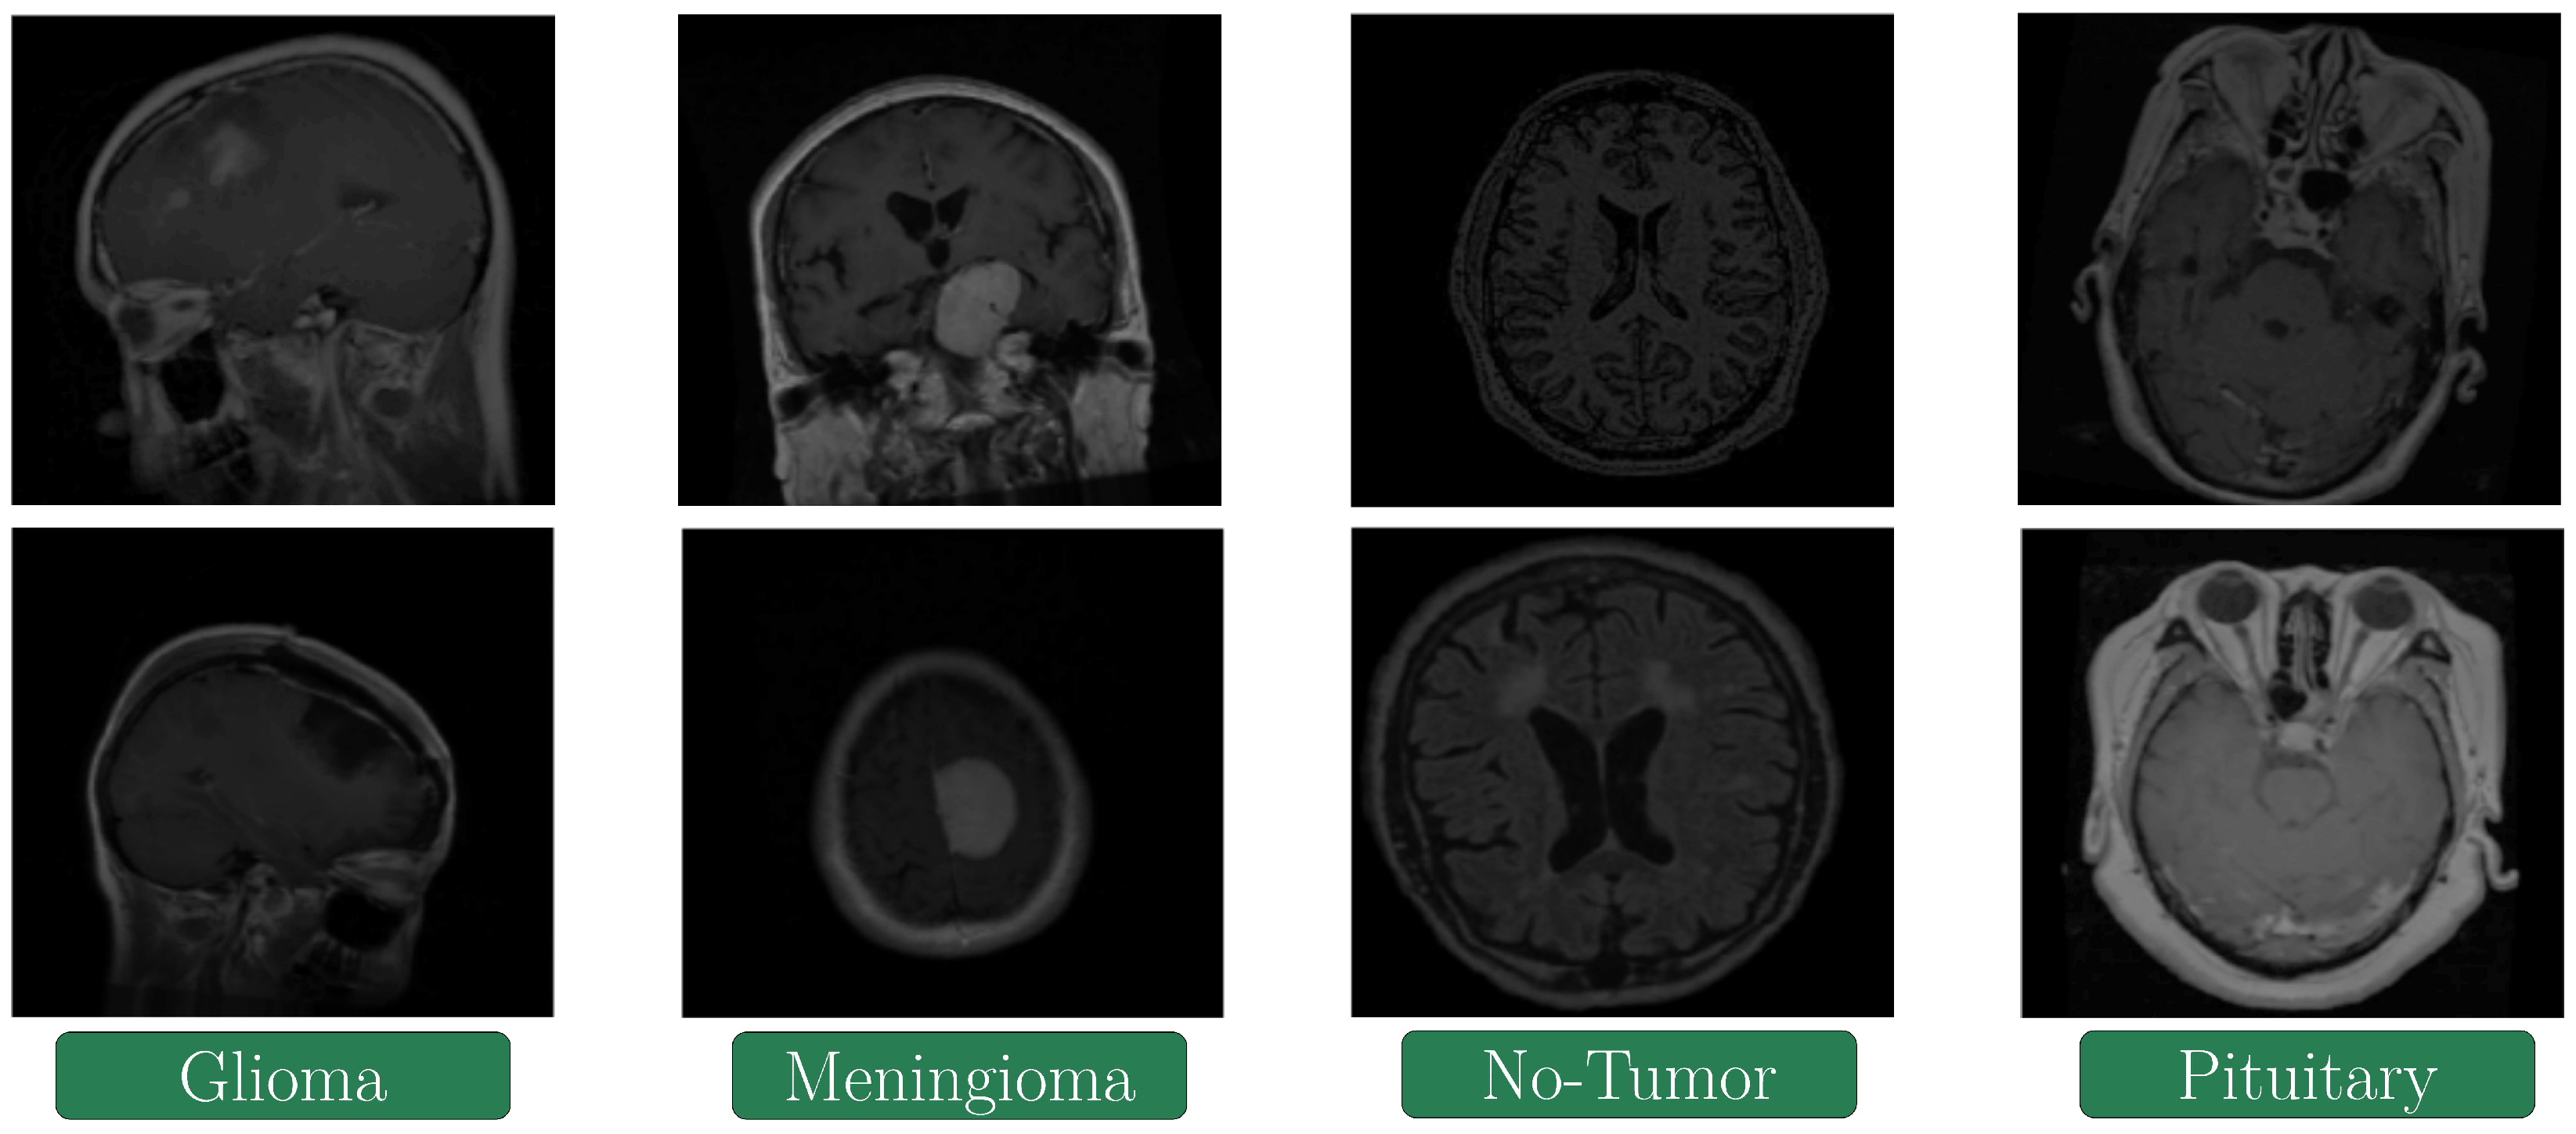

The details associated with the dataset are displayed in Table 4. This dataset contains 7023 MRIs of the human brain of different types in grayscale and JPG format. The four classes of brain tumors shown in the dataset are Glioma (with 1321 images for training and 300 for testing), Meningioma (with 1339 images for training and 306 for testing), No-tumor (with 1595 images for training and 405 for testing) and Pituitary (1457 images for training and 300 for testing). For the training and validation task, 80% and 20% of the images were used, respectively. However, in the preprocessing stage, Resizing and Data Augmentation were applied to the dataset to provide an adequate input size for each different model and increase the number of images to be used. This resulted in 9139 images, of which 70% of the dataset was used for training and 30% was used for testing.

The images of the no-tumor class were extracted from the Br35H dataset. The Glioma class images in the SARTAJ dataset are incorrectly classified. Hence, they have been replaced by images from the dataset in the reference [49]. Figure 7 depicts some instances of the images stored inside the database:

Figure 7. Sample of the MRIs in the dataset.